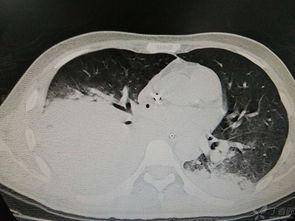

肝脏是人体内最大的实质性器官,具有强大的再生能力。正常情况下,一个成年人的肝脏大约重1.5千克,其中大约有25%的肝脏组织就可以再生出完整的肝脏。所以,理论上,移植半个肝脏是完全可行的。

1. 肝脏再生能力:正如前面提到的,肝脏具有强大的再生能力,移植半个肝脏后,剩余的肝脏组织可以再生出完整的肝脏。